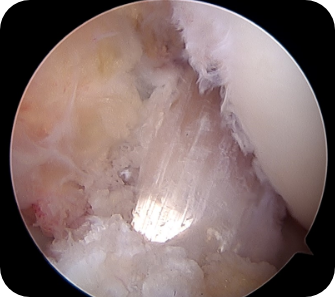

• ▲ 무릎 연골판 봉합술 전

• ▲ 무릎 연골판 봉합술 후

• 2) 관절경하 연골판 봉합술

반월상 연골판 파열 중, 파열된 부분의 혈류공급이 원활하고, 파열면의 상태가 깨끗하여 봉합 시 다시 붙을 가능성이 있는 경우에 찢어진 연골판의 두 부분을 실이나 기구를 이용하여 봉합해 주는 방법입니다.

수술방법

관절내시경을 이용하여 무릎 안을 보면서 여러 기구로 찢어진 부위를 봉합합니다.

수술장점

연골판을 파열전의 모양 및 기능으로 회복시키는 수술입니다. 봉합하여 잘 붙는 경우 파열전의 상태와 똑같은 상태로 돌아갈 수 있습니다. 물론, 봉합된 부위가 붙을 가능성이 떨어지는 경우에는 권하기 힘들며, 부분 절제술, 연골판 이식술 등 다른 수술 방법을 고려해야 합니다.